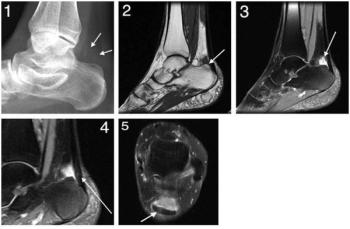

MRI reveals cause of heel painByTiana Crawford, MS-IV,Richard Desruisseau, MDOctober 14th 2010A 51-year-old woman presented to the clinic complaining of left heel pain.Tenderness and soft tissue swelling were observed. MRI reveals Haglund's deformity.